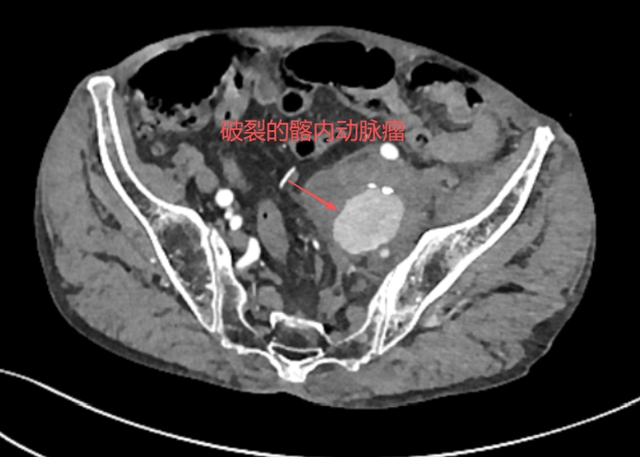

张大爷以为休息一下会好转,但疼痛不仅没有减轻,反而逐渐加重。家人见他面色苍白、满头冷汗,立即将他送往当地医院。CT平扫结果让人心头一紧:左侧髂内动脉瘤破裂。这是个危急情况,当地医院迅速将张大爷转入西南医科大学附属中医医院介入·血管科。

当张大爷抵达医院时,情况已经相当危急,介入·血管科徐燕能博士立即接手处理,迅速安排全腹部血管造影检查(CTA),进一步明确诊断——左侧髂内动脉瘤已经破裂。